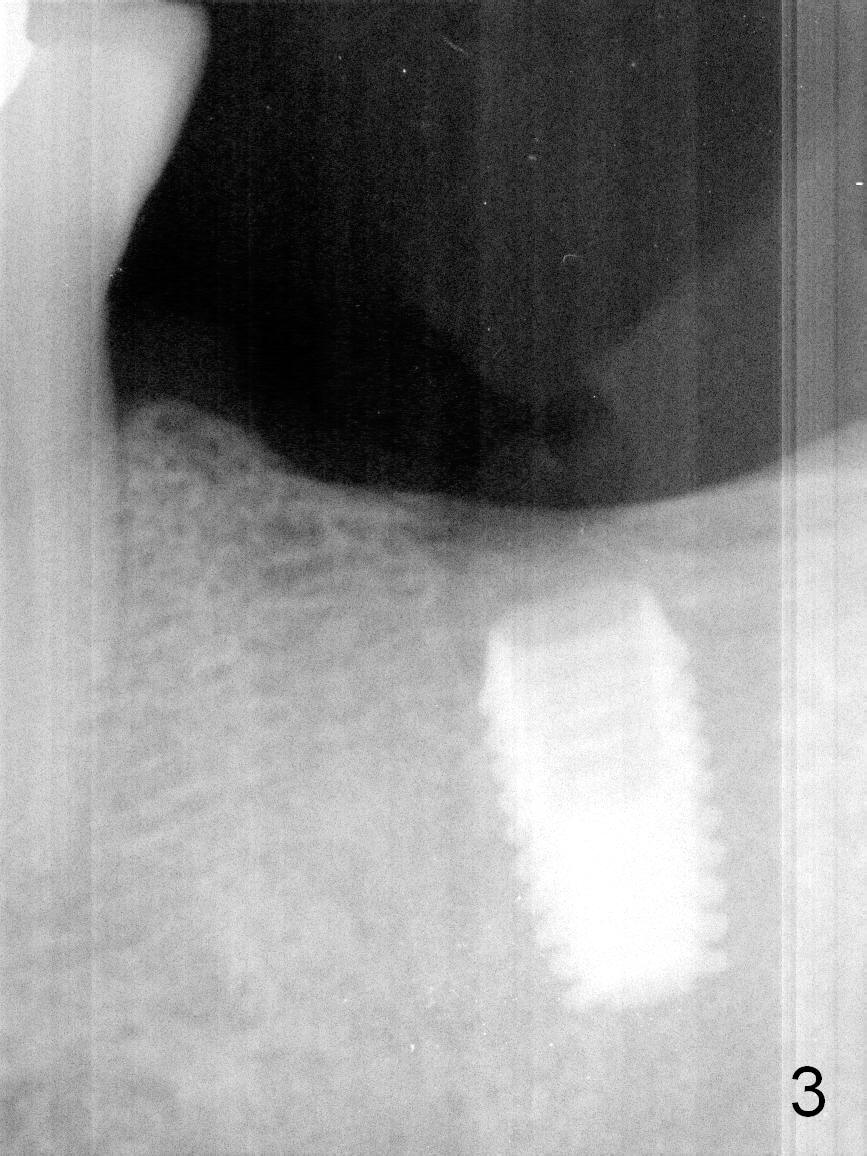

Implant Placed for Opposing Tooth Intrusion

A 4.5x8 mm Bicon implant is placed (Fig.1-3) with intent to intrude the supraerupted opposing tooth once a provisional is fabricated. Now it is 5 months postop. In spite of poor implant position, the abutment or the crown has not become loose with increased bone density around the implant 2 years 3 months post cementation (Fig.4: *). Guide could easily overcome the deficiency.